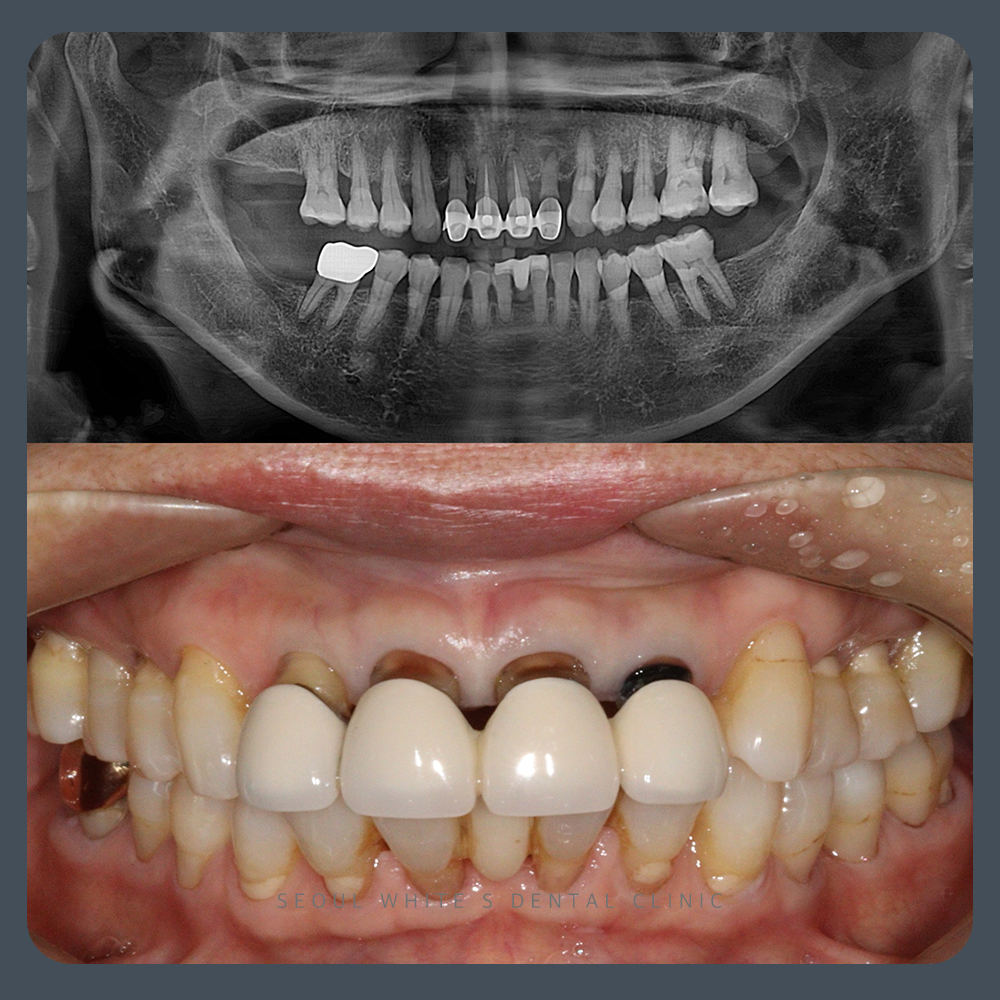

술전 사진

23.01.27

상악 전치부에서 보실 수 있듯이, 기존 브릿지 아래쪽의 뼈가 모두 소실되어 환자분이 웃을 때 치아 뿌리가 드러나는 상태였습니다. 단순히 치아 뿌리가 노출된 상태라면 일부 치료를 통해 회복이 가능할 수 있지만, 이미 하방에 심각한 우식이 발생해 색이 어두워지고, 기존 수복물은 더 이상 유지할 수 없는 상황이었습니다.

더욱이 주변 뼈까지 소실되면서 치아의 동요가 발생했고, 기존 브릿지를 재설치할 수 있는 상태가 아니었습니다. 따라서, 주변 뼈를 다시 채우는 골이식 수술을 진행하며, 전치부 브릿지 임플란트 치료를 계획하게 되었습니다.